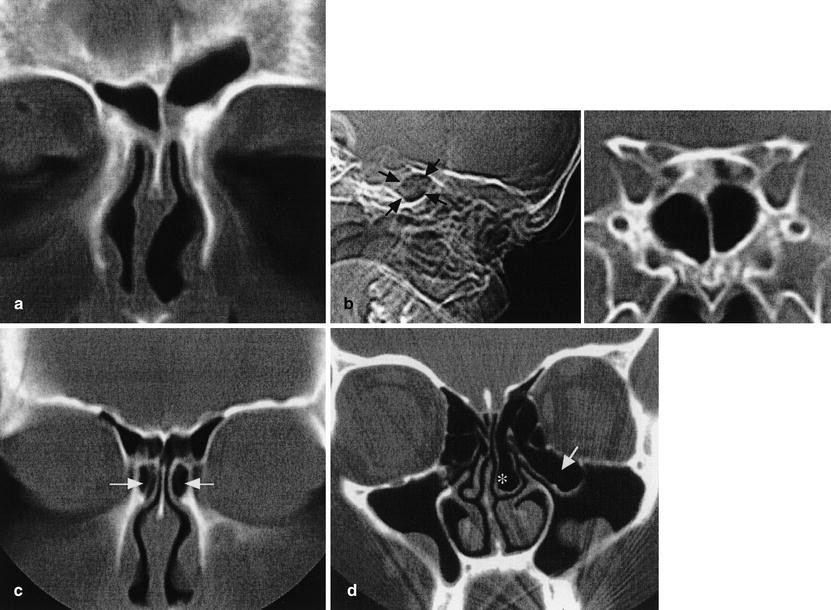

1 bab 1 pendahuluan 1. 1 latar belakang kanker serviks adalah salah satu penyakit kanker yang berbahaya bagi kaum wanita diseluruh dunia terutama di negara berkembang. kanker serviks sampai saat ini, masih menjadi penyebab kematian akibat kanker terbanyak didunia setelah kanker payudara. Your doctor will feel for tenderness in your nose and face and look inside your nose. methods for diagnosing chronic sinusitis include: 1. imaging tests. images taken using ct or mri can show details of your sinuses and nasal area. these might pinpoint a deep inflammation or physical obstruction that's difficult to detect using an endoscope. 2. looking into your sinuses. a thin, flexible tube with a fiber-optic light inserted through your nose allows your doctor to see the inside of your sinus

Jun 10, 2020 · medically known as rhinosinusitis, a sinus infection occurs when your nasal cavities become infected, swollen, and inflamed. sinusitis is usually caused by a virus and often persists even after. Feb 10, 2021 · sinusitis or sinus infection is inflammation of the air cavities within the passages of the nose. sinusitis can be caused by infection, allergies, and chemical or particulate irritation of the sinuses. most people do not spread sinus infections to other people. For sinusitis lasting more than 12 weeks, a ct scan is recommended. on a ct scan, acute sinus secretions have a radiodensity of 10 to 25 hounsfield units (hu), but in a more chronic state they sinusitis t become more viscous, with a radiodensity of 30 to 60 hu. nasal endoscopy and clinical symptoms are also used to make a positive diagnosis. Hipertensi porta adalah peningkatan tekanan dalam sistem vena porta yang disebabkan oleh adanya tahanan (resistensi) aliran darah di sistem porta. vena porta merupakan vena penghubung vena intestinal dan vena lienalis dengan hepar.